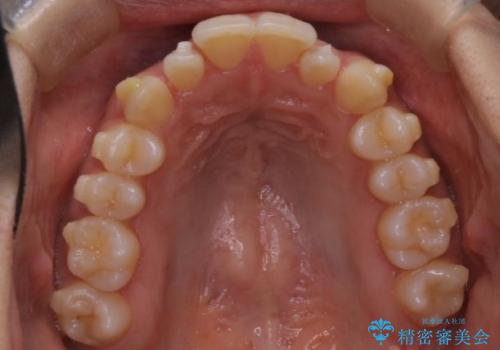

反対咬合と前歯のガタガタを非抜歯で改善

- 患者様は、上下の前歯のガタガタと反対咬合(下の歯が上の歯より前に出ている状態)を主訴として来院されました。診断の結果、抜歯を行わずに治療を進めるため、臼歯を遠心移動させてスペースを作り、IPR(インタープロキシマルリダクション)で歯間を調整する治療計画を立てました。インビザラインを使用して、透明で目立たない矯正装置により、歯列を整えながら噛み合わせも改善することを目標としました。

非抜歯での治療では、限られたスペースの中で効率的に歯を動かす必要があります。本症例では、臼歯を後方に移動させる遠心移動を行い、歯列のガタガタを改善しました。また、IPRを適切に行うことでスペースを確保し、歯根や歯肉への負担を最小限に抑えながら治療を進めました。インビザラインを使用することで、治療中も目立ちにくく、患者様の日常生活への影響を軽減しました。結果として、抜歯を行わずに美しい歯並びと自然な噛み合わせを実現し、患者様には大変満足していただけました。